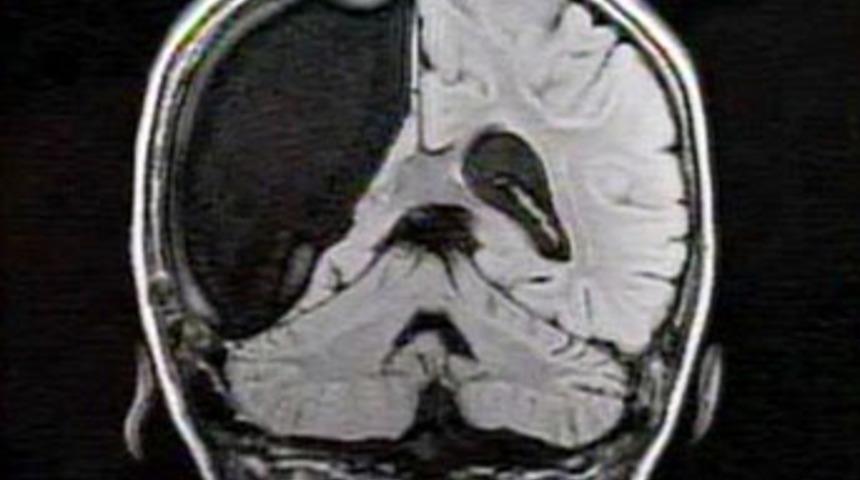

Dokuz yaşındaki Cameron Mott'un beyninin yarısı ameliyatla alındı.

Üç yaşında beyninin sağ tarafını 'yiyen' bir hastalık olan Rasmussen sendromuna yakalanan Cameron, sara nöbetleri geçirmeye başladı. Doktorlar sonunda ancak küçük kızın beyninin yarısının alımasıyla bu hastalığın önüne geçilebileceğini söyledi. Doktorlar, beynin sol tarafını yöneten sağ tarafını almanın ameliyattan çıktığında küçük kızın felç kalacağı anlamına geldiğini biliyordu. Ancak doktorlar çocukların beyinlerinin yeniden sinirlere bağlanma ve fonksiyonları üstlenme kapasitesine sahip olduğunu da biliyorlardı.